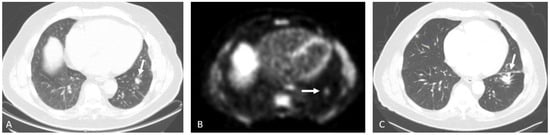

Detection of Loco-Regional Disease and Distant Metastases